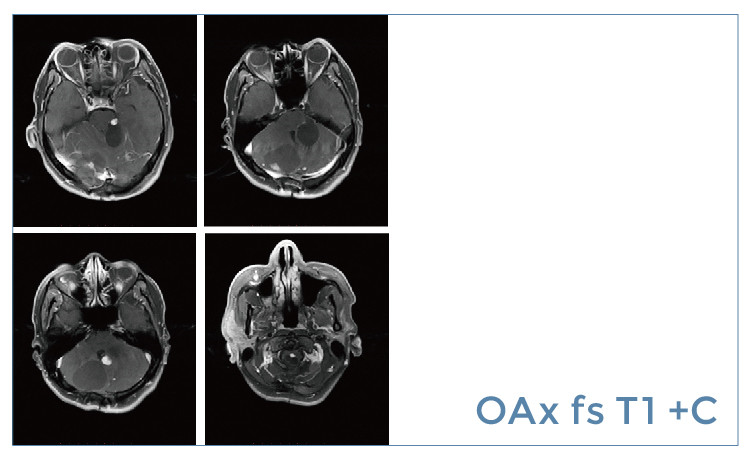

【朗润影像档案】20190614磁共振影像病例结果讨论